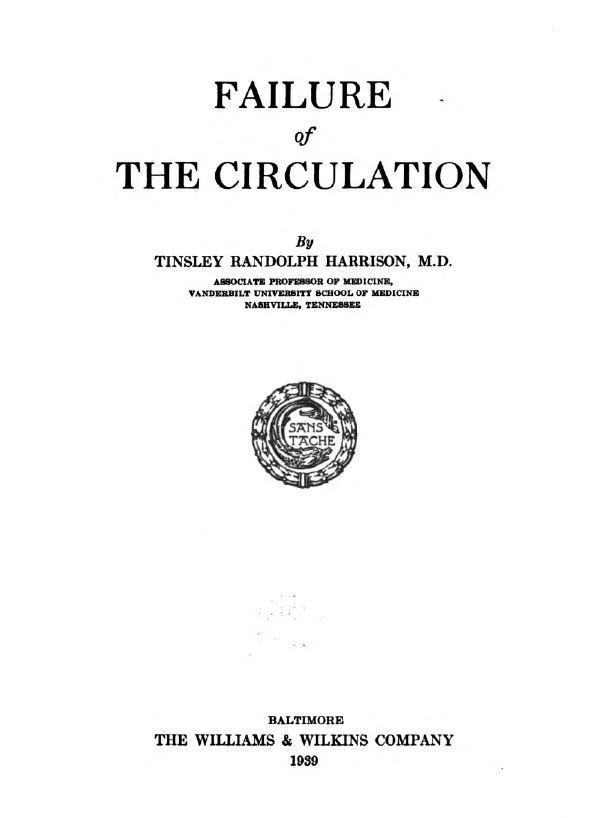

The Good Doctor: Tinsley R. Harrison - from MMI Archives

Tinsley R. Harrison | Encyclopedia of Alabama

Tinsley R. Harrison, M.D.: Teacher of Medicine - bio - by Jim Pittman - 2014

Tinsley Harrison, MD: Teacher of Medicine - notes, pics, timelines - PDF

The Principles of Therapy in Patients with Congestive Heart Failure - Tinsley R. Harrison, M.D. - NEJM - September 17, 1936

Vanderbilt Medicine - The Dynamic Duo - Al Blalock / Tinsley Harrison